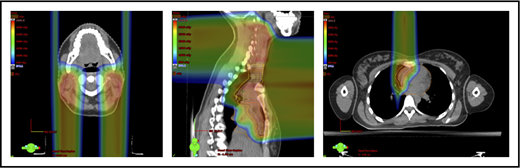

Plans for PBSPT with a single-field uniform dose and a gradient match, with anterior and posterior beams used to treat disease that involves the bilateral upper neck and the mediastinum (disease anterior to the right heart).

With regard to field arrangements, the PBSPT technique for an anterior upper mediastinal and lower neck target usually requires 1 (repainted) or 2 anterior fields. For more complex target volumes, targets can be divided into 2 or more parts (eg, neck CTV, mediastinal CTV, and axillary CTV), and a multifield plan can be used (Figure 5). For cases that involve lower (posterior) and upper (anterior) mediastinal targets, a combination of posterior and anterior fields can maximally spare the heart and lungs (Figure 6). For upper neck targets, lateral or posterior fields can avoid the oral cavity/salivary structures. For axillary targets, a posterior field can help to spare breast tissue. Although these various field arrangements can be used in PSPT, gradient matching is simpler in PBSPT when the fields overlap or oppose, obviating the need for feathering.